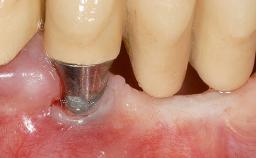

It is sometimes necessary to remove and replace compromised implants. This case is a clear example of the need for multiple steps to achieve an optimal therapeutic result for patients with non-salvageable implants. It illustrates how the lost soft and hard tissues were rebuilt in a sequence that improved the healing of the hard tissues and assured their long-term stability. The 35-year-old healthy patient presented with clinical attachment loss on the proximal and lingual surfaces of the natural dentition. Some gingival recession was present on natural teeth, particularly in the posterior sextants (S1, S3, S4, and S6).

| Bone Augmentation | Horizontal|Staged|Vertical |

| Augmentation Materials | Autogenous chips|Autogenous block(s)|Xenogenous |